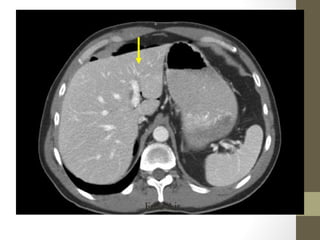

Kidney Stones- CT

Style

Radiology- CT Scan •Detect leaking AAA (in stable patient) • Evaluate for renal calculi, appendicitis, perforation (free air), diverticulitis, abscess, mesenteric ischemia, masses, obstruction • Sensitivity and specificity vary • Not a place for unstable patients • Contrast • PO and IV contrast in most patients • sometimes rectal contrast is helpful to look for large bowel problems (appendicitis) • In patients with renal insufficiency • give IV contrast judiciously in patients • consider ultrasound as an alternative if possible • a creatinine > 1.5 usually requires bicarbonate and fluid hydration to minimize contrast nephropathy

• 38.